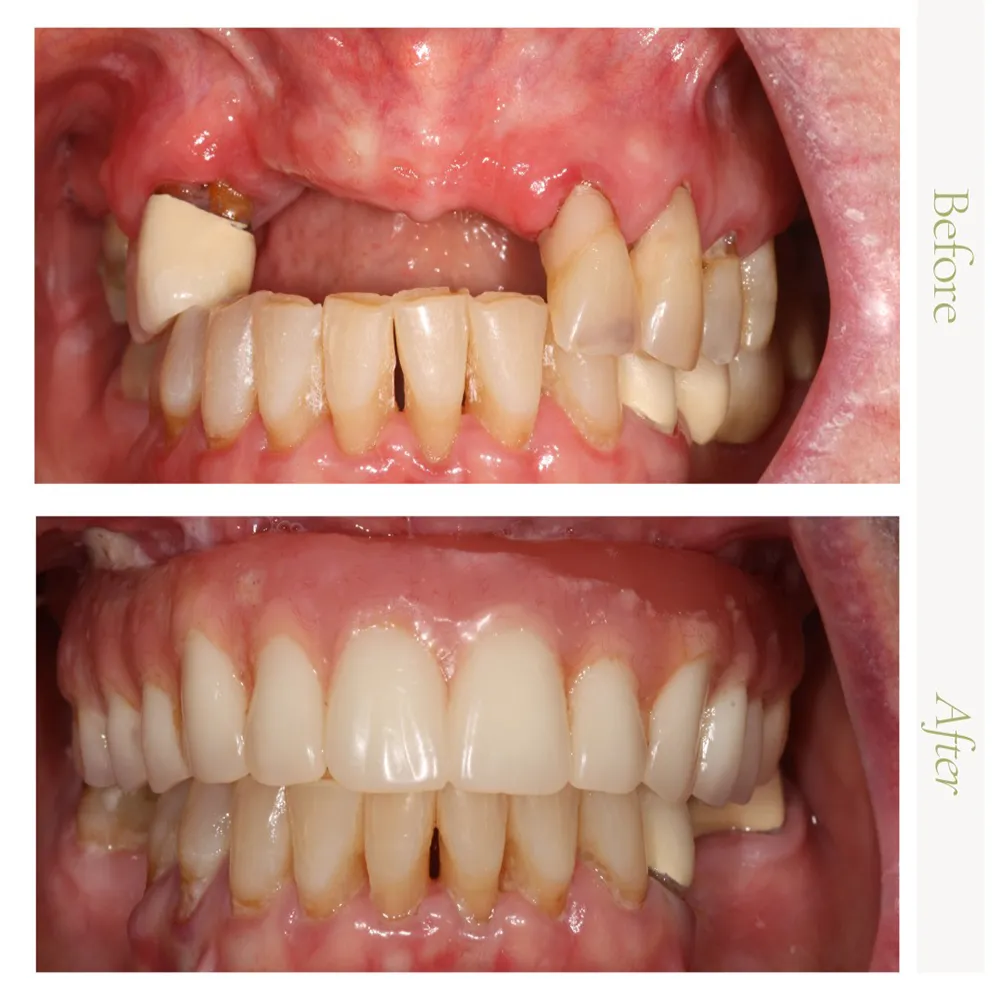

In the gallery below, you’ll find a selection of real patient results that reflect the quality and precision of our surgical care. If you’re inspired by the transformations you see and are considering a visit, we invite you to contact our office at 623-931-9197. A member of our team will be glad to assist you in scheduling your consultation.